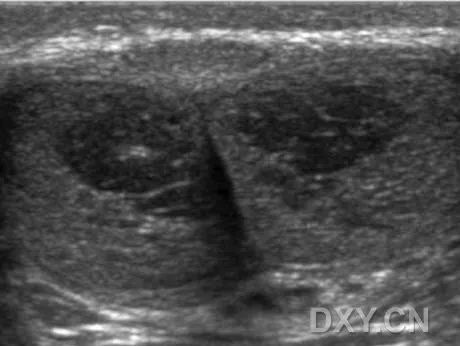

C 当阴茎完全勃起时其表现为阴茎海绵体内的细小网格样结构。

在阴茎处于最大硬度时,阴茎海绵体内可看到纤细的网格样回声,是由于有海绵体窦界面。

阴茎根部的海绵体窦间隙正常情况下要比其他阴茎干部分明显。海绵体窦内的血液经常表现为点状回声。